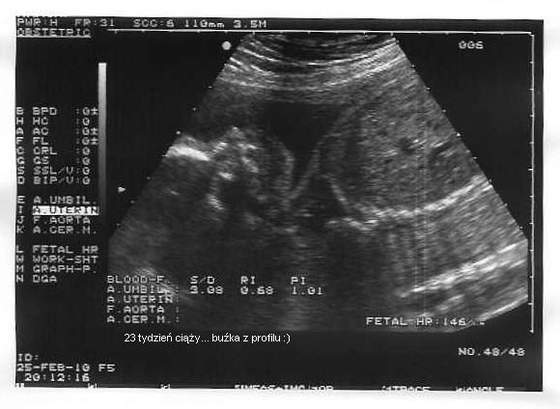

cudowny mały skarbuś :-)